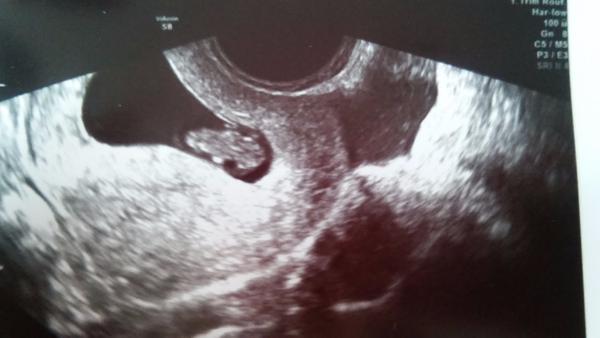

jinak moje POSLEDNÍ kontrola v centru dopadla na výbornou. Jsem 7+2 a mimčo odpovídá 7+5, tak je i maličko napřed. Už mě předali do péče mého gynekologa. Mam tam akorát malý hematom, který se už prý vstřebává, tak od tud mohlo být to špinění. Pomalu už začnu i vysazovat léky a z píchacího Agolutinu na Utrogestan, což nemám moc radost 🙂 Malý/á vypadá jak žabička 😉

To je krásna první fotecka miminka. Super, užívej si to moc moc.

@briketaaaa Krasnyy. Mám radost 😀

@briketaaaa krásný mimísek, gratulujůů 😉